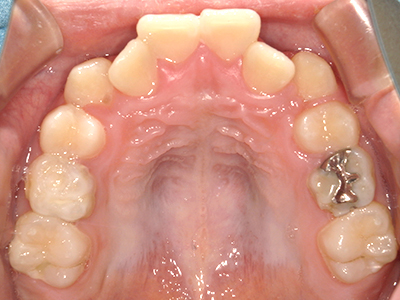

矯正装置を装着し、調整しながら少しずつ歯を移動させ、歯並びを整えていきます。